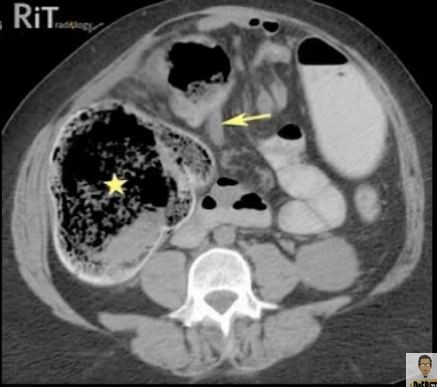

Às vezes só o tamanho das ansas não chega e é difícil distinguir colon de delgado na TC. Ai, devemos olhar para o conteúdo das ansas: No delgado o conteúdo é muito homogéneo, como se vê nesta imagem no lado esquerdo do doente, por outro lado,no colon o conteúdo é bastante heterogéneo, como se vê tanto na grande dilatação, assinalada pelo asterisco, como na ansa, não tão dilatada, mais à frente. Isto deve-se a duas coisas: 1º, e mais óbvio, há ar no colon, devido à acção das bactérias, que se vê a preto. 2º, no colon vai havendo a reabsorção de água, logo vai ser uma zona em que vão estar misturadas fezes sólidas, com fezes líquidas, com fezes assim assim, e isso vai dar diferentes radiodensidades :)